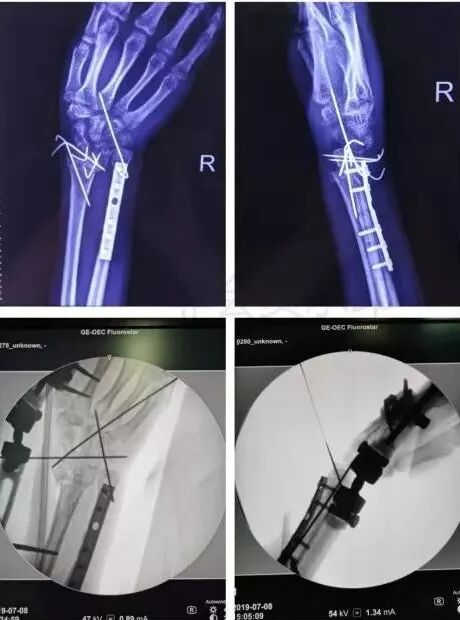

5)前臂骨折(尺骨,桡骨,或双骨折)

图片

• 闭合或开放性骨折均争取伤后6-8h完成。

• 手术后延,尺骨-桡骨骨桥形成风险概率高。

7)手部骨折

• 无论闭合或开放性骨折,均应早期复位内固定。

• 合并神经,血管,肌腱损伤,紧急手术。